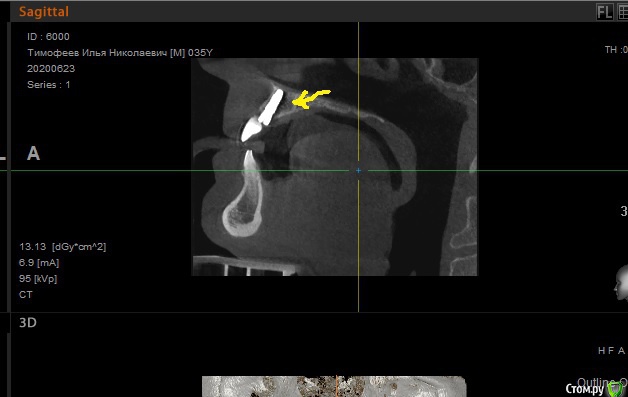

Илья Т. Опубликовано 17 июля, 2020 Автор Поделиться Опубликовано 17 июля, 2020 (изменено) Доброе утро! А подскажите ещё, поставили временную коронку на имплант, но она немного светлее остальных зубов, доктор сказал, что со временем немного потемнеет и что ее типа с запасом сделали по цвету, она правда потемнеет (сейчас она выделяется)? Просто обычно же по цвету подбирают с помощью специальных образцов?И еще доктор сказал, что рассматривая КТ что то увидел на 7 зубе, он живой или мертвый? Изменено 17 июля, 2020 пользователем Илья Т. Ссылка на комментарий

Irouil Опубликовано 17 июля, 2020 Поделиться Опубликовано 17 июля, 2020 доктор сказал, что со временем немного потемнеетЧаще всего так и бываетИ еще доктор сказал, что рассматривая КТ что то увидел на 7 зубе, он живой или мертвый?Если речь о нижнем зубе, то надо посмотреть оригинал томограммы, возможно просто в этом месте верхушки корней находятся в краю челюсти 1 Ссылка на комментарий

Илья Т. Опубликовано 17 июля, 2020 Автор Поделиться Опубликовано 17 июля, 2020 Чаще всего так и бываетЕсли речь о нижнем зубе, то надо посмотреть оригинал томограммы, возможно просто в этом месте верхушки корней находятся в краю челюстиДа нижняя 7-ка. Вот ссылка на оригинал КТ: https://yadi.sk/d/8OstTe5zOj4kLgБольшое спасибо за ответы) Ссылка на комментарий

Irouil Опубликовано 17 июля, 2020 Поделиться Опубликовано 17 июля, 2020 Мёртвый зуб, требуется эндодонтическое лечение, у верхушек корней воспалительный процесс 1 Ссылка на комментарий

Илья Т. Опубликовано 17 июля, 2020 Автор Поделиться Опубликовано 17 июля, 2020 Мёртвый зуб, требуется эндодонтическое лечение, у верхушек корней воспалительный процессА как так могло получиться? Он не беспокоит, внешне выглядит отлично (не потемнел). И давно вообще это могло с ним случиться? Ссылка на комментарий

Irouil Опубликовано 17 июля, 2020 Поделиться Опубликовано 17 июля, 2020 А как так могло получиться? Он не беспокоит, внешне выглядит отлично (не потемнел). И давно вообще это могло с ним случиться?Из-за глубокого кариеса в зубе развился бессимптомный хронический пульпит, потом кариес вылечили, наложили пломбу, но пульпит себя так и не проявил и плавно перешёл в хронический периодонтит - то, что происходит вокруг зуба сейчас 1 Ссылка на комментарий